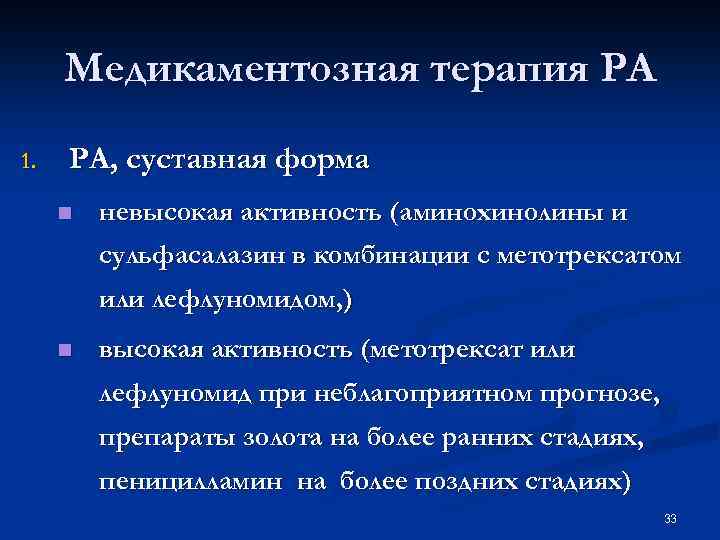

Медикаментозная терапия РА 1. РА, суставная форма n невысокая активность (аминохинолины и сульфасалазин в комбинации с метотрексатом или лефлуномидом, ) n высокая активность (метотрексат или лефлуномид при неблагоприятном прогнозе, препараты золота на более ранних стадиях, пеницилламин на более поздних стадиях) 33

Медикаментозная терапия РА 1. РА, суставная форма n невысокая активность (аминохинолины и сульфасалазин в комбинации с метотрексатом или лефлуномидом, ) n высокая активность (метотрексат или лефлуномид при неблагоприятном прогнозе, препараты золота на более ранних стадиях, пеницилламин на более поздних стадиях) 33